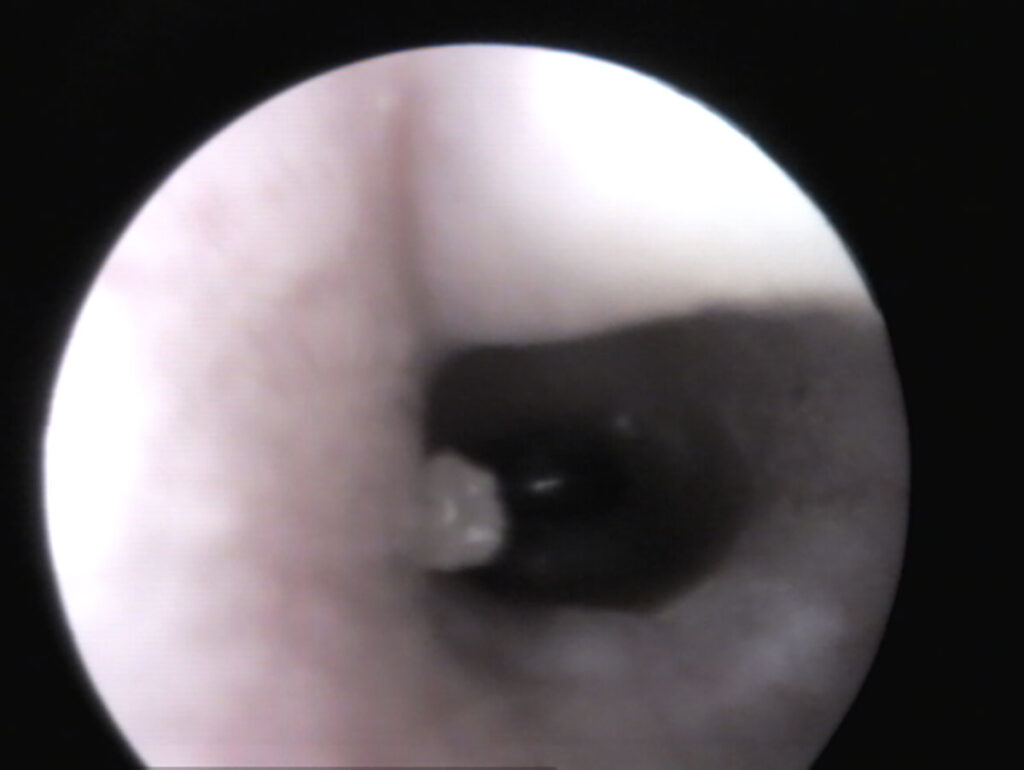

In un orecchio sano, tirando delicatamente il padiglione auricolare verso l’alto (Fig. 1), si riesce solitamente a vedere fino al timpano (Fig. 3). Se è presente materiale nel condotto uditivo, è importante distinguere se si tratta “solo” di cerume accumulato (bianco in profondità, giallastro verso l’orifizio) e il condotto uditivo è altrimenti normale, oppure se sono presenti segni di infiammazione (arrossamento, gonfiore, lesioni, liquefazione del secreto) (Fig. 4) e possibili cause primarie come corpi estranei e/o ectoparassiti.

Fig. 3: Vista del timpano (pars tensa – trasparente, pars flacida – tessuto) di un coniglio

Fonte: J. Hein